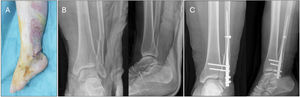

Example of a fibular fracture treated with a second-generation intramedullary nail due to soft tissue involvement. (A) Clinical image showing severe soft tissue injury (open fracture wound). (B) Preoperative X-rays showing bifocal fibula fracture. (C) Postoperative X-rays showing second generation nail fixation and trans-syndesmotic fixation with 2 screws through the nail.